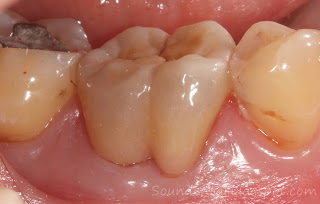

裝戴後之口內視角。

裝戴後一周追蹤。可見牙根分叉處健康飽滿的牙齦,此處現在可以用牙刷輕鬆維持清潔。